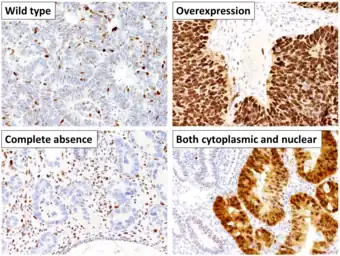

In 10–20% of endometrial cancers, mostly Grade 3 (the highest histologic grade), mutations are found in a tumor suppressor gene, commonly p53 or PTEN. In 20% of endometrial hyperplasias and 50% of endometrioid cancers, PTEN has a loss-of-function mutation or a null mutation, making it less effective or completely ineffective.[37] Loss of PTEN function leads to up-regulation of the PI3k/Akt/mTOR pathway, which causes cell growth.[22] The p53 pathway can either be suppressed or highly activated in endometrial cancer. When a mutant version of p53 is overexpressed, the cancer tends to be particularly aggressive.[37] P53 mutations and chromosome instability are associated with serous carcinomas, which tend to resemble ovarian and Fallopian carcinomas. Serous carcinomas are thought to develop from endometrial intraepithelial carcinoma.[22]

PTEN and p27 loss of function mutations are associated with a good prognosis, particularly in obese women. The Her2/neu oncogene, which indicates a poor prognosis, is expressed in 20% of endometrioid and serous carcinomas. CTNNB1 (beta-catenin; a transcription gene) mutations are found in 14–44% of endometrial cancers and may indicate a good prognosis, but the data is unclear.[37] Beta-catenin mutations are commonly found in endometrial cancers with squamous cells.[22] FGFR2 mutations are found in approximately 10% of endometrial cancers, and their prognostic significance is unclear.[37] SPOP is another tumor suppressor gene found to be mutated in some cases of endometrial cancer: 9% of clear cell endometrial carcinomas and 8% of serous endometrial carcinomas have mutations in this gene.[39]

- ↑ Köbel M, Ronnett BM, Singh N, Soslow RA, Gilks CB, McCluggage WG (January 2019). "Interpretation of P53 Immunohistochemistry in Endometrial Carcinomas: Toward Increased Reproducibility". International Journal of Gynecological Pathology. 38 (Suppl 1): S123–S131. doi:10.1097/PGP.0000000000000488. PMC 6127005. PMID 29517499.